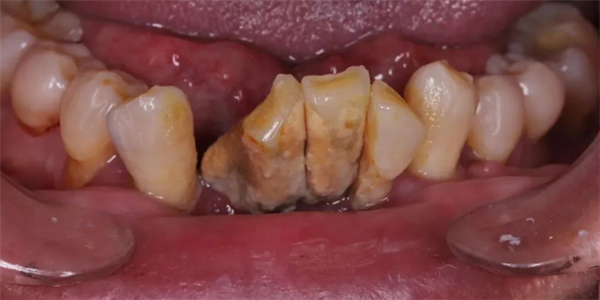

大量牙结石,导致牙齿松动移位,图源:作者提供 大量牙结石,导致牙齿松动移位,图源:作者提供 再再后来,牙齿不仅仅松动了,它们可能还开始移动位置了——牙齿和牙齿之间的缝隙越来越大。而之前松动的牙齿开始摇摇晃晃,有的还会出现牙齿的疼痛!这时候再不看牙,光想着吃点药止一下痛,其实已经无济于事了。牙根开始暴露出来,牙齿的松动越来越严重。

速读:跟蛀牙、牙髓炎这些病情发展会导致牙齿疼痛的病不一样,更多的时候,牙周炎的发展开始的时候非常非常缓慢,就像温水煮青蛙,没有特别明显的急性症状,这也是很多年轻人在疾病刚刚开始的时候并不在意的原因。 大量牙结石,导致牙齿松动移位,图源:作者提供。 而之前松动的牙齿开始摇摇晃晃,有的还会出现牙齿的疼痛! 由于牙龈退缩,牙齿之间形成了黑三角,此时要治疗和改善已经非常困难,图源:作者提供。 另外,药物在牙周炎治疗中的作用,经常不是吃的——漱口是常见的药物使用方法,另外一种则是把药物塞在牙齿周围的沟里,局部发挥抗菌作用。